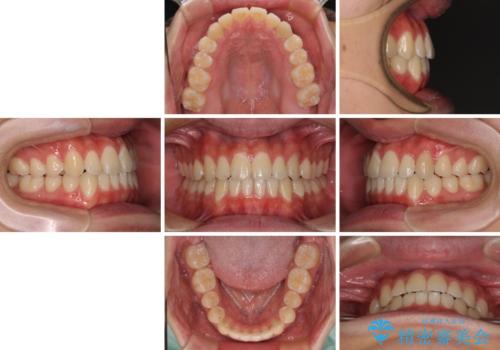

- 前歯のデコボコを治したいとのことで来院された患者様です。

受け口傾向の骨格であり、前歯はクロスバイトまたは切端咬合となっており、叢生は警備であったため、下顎を中心に歯列全体の後方移動を行い、IPR(歯と歯の間を削る)によってデコボコが解消するように設計し、インビザラインにより治療を行うこととしました。

受け口傾向のインビザライン矯正は比較的治療を行いやすいため、きれいに仕上げることができました。舌の突出癖が顕著であったため、改善のためのトレーニングをしっかりと行っていただきました。